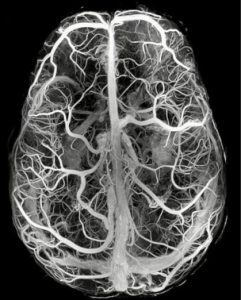

Științific s-au observat aceste schimbări prin EEG (electroencefalogramă), aparat ce măsoară activitatea creierului. Pe măsură ce adolescenții se dezvoltă, semnalul EEG devine mai slab ca intensitate, dar gândurile devin mai organizate și mai coerente. Asta arată că mintea tinerilor devine mai eficientă, capabilă să gândească mai clar și să proceseze informațiile mai repede.

Somnul este esențial, mai ales în anii adolescenței, deoarece materia cenușie, partea creierului care conține neuroni, se micșorează din ce în ce mai mult, iar materia albă, care leagă zonele creierului, se mărește. Acest factor determină ca informațiile să circule mai rapid în creier.

Cercetările arată că somnul are legătură directă cu inteligența și capacitățile cognitive ale adolescenților. În timpul somnului, creierul produce fusuri de somn, scurte pulsații care ajută la conectarea diferitelor zone ale creierului.

Adolescenții care au fusuri de somn mai puternice și mai bine coordonate au, de obicei, rezultate mai bune la logică, concentrare și autocontrol. Practic, fusurile de somn arată cât de bine comunică diferitele părți ale creierului între ele și cât de eficient funcționează mintea. Somnul nu doar odihnește, ci construiește și întărește abilitățile cognitive ale adolescentului.

În timpul somnului profund, undele lente din creier se mută din partea occipitală a creierului, spre partea frontală, unde se formează gândirea logică, autocontrolul și luarea deciziilor.